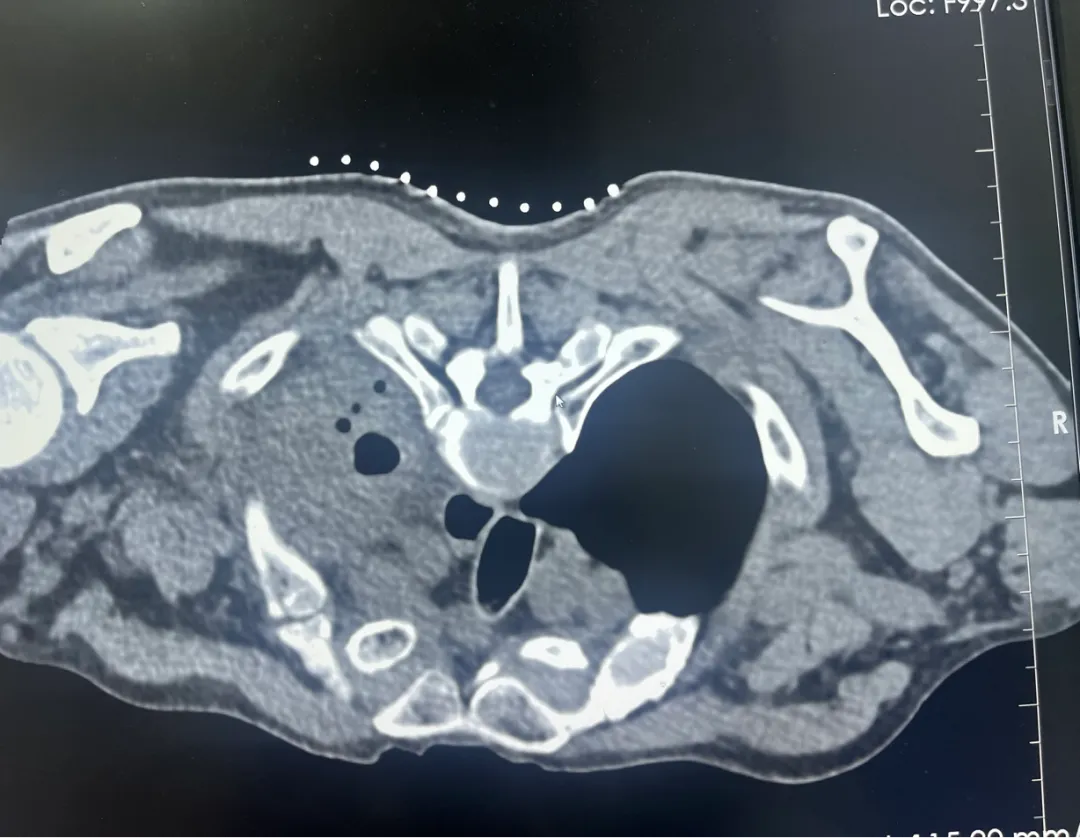

2.CT扫描,制定穿刺路径,以精确定位穿刺点位置、角度、深度。

3.充分局部麻醉,采用专用活检针进行穿刺,获得1-3条肺部病变组织进行病理分析/病原菌培养。

4.术后卧床休息,给予吸氧,观察生命体征,观察有无咯血、气胸等常见并发症,如果出现并发症,给予积极处理,一般穿刺后1-2天出院。